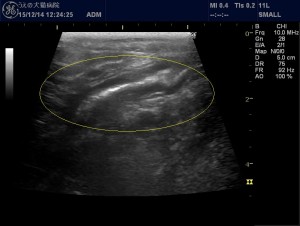

こちらは腸の別の部分の超音波画像です。

黄色丸で囲った部分が異常な腸の部分で、コルゲートサインと呼ばれる腸の内腔がウネウネした所見がみられます。これだけでは膵炎と診断できませんが、他の検査も行うことで膵炎と診断できました。